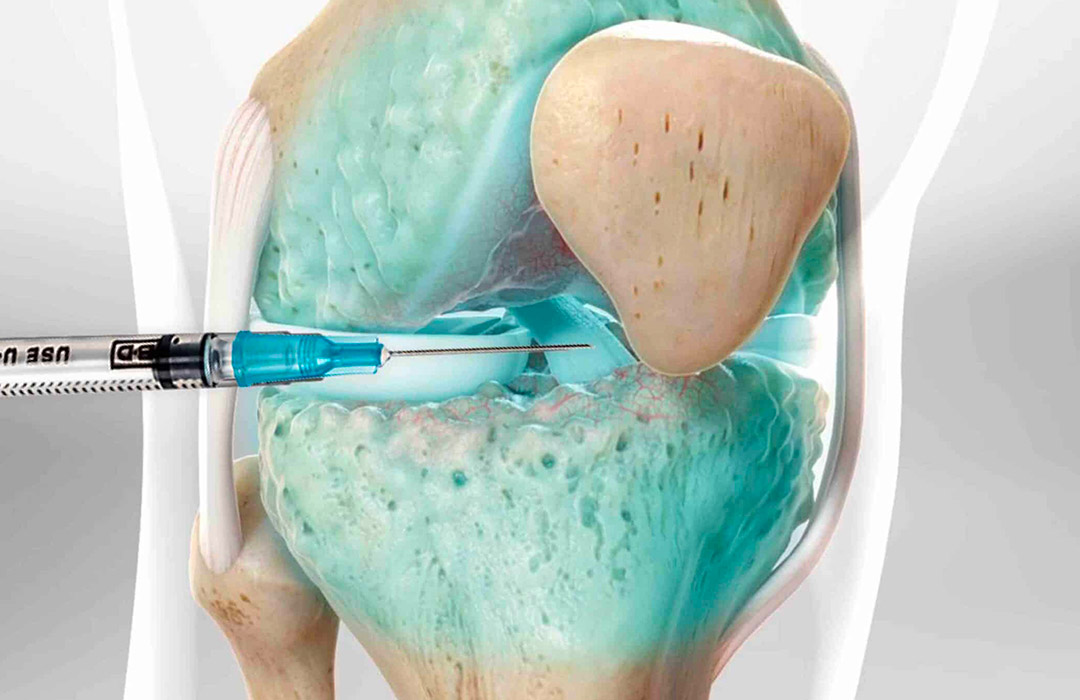

A aplicação de ácido hialurônico no joelho é um tratamento moderno e seguro indicado para aliviar dores e melhorar a mobilidade em casos de artrose e desgaste da cartilagem.

O procedimento ajuda a restaurar a lubrificação natural da articulação, reduzindo o atrito entre os ossos.

o ácido hialurônico diminui o atrito entre os ossos e melhora a lubrificação da articulação, proporcionando alívio rápido e duradouro.

o tratamento ajuda a restaurar o equilíbrio do líquido sinovial, nutrindo e protegendo a cartilagem articular.

A aplicação é minimamente invasiva e feita com anestesia local. O desconforto é leve e bem tolerado pela maioria dos pacientes.